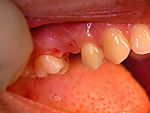

Die folgenden Patientenfälle sollen Ihnen einen Einblick in die Möglichkeiten der modernen Implantation geben.

Sofort-Implantation: